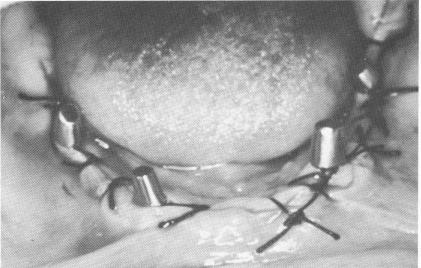

The tissues were adapted and sutured with simple surgical ties (Fig. 11-141) . When the sutures were removed (Fig. 11-142), the patient's old denture was hollowed out, lined with a soft tissue reliner, and used as a temporary splint until the final prosthesis could be fabricated (Fig. 11-143).

Fig. 11-141. The tissues were sutured over the implants.